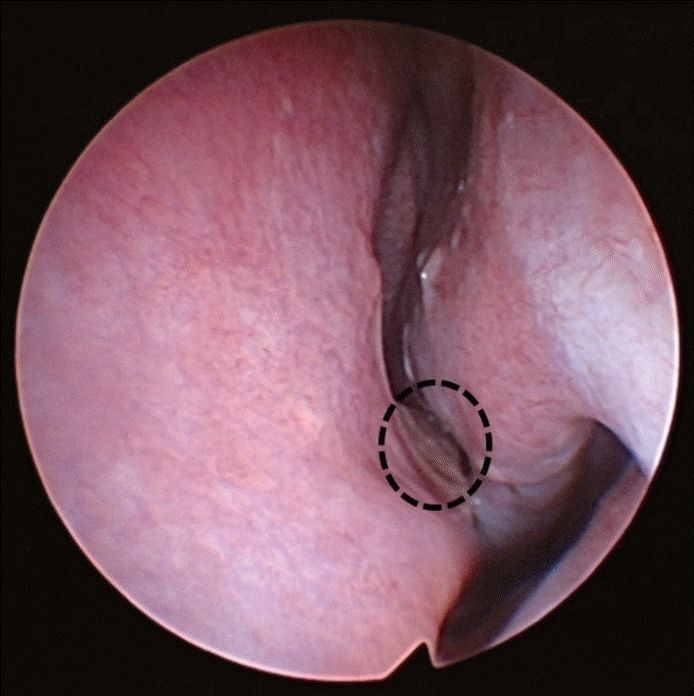

A female in their 70s presented to our clinic with left hemifacial pain, which had developed four months prior. The patient had previously received a COVID-19 nasopharyngeal swab through her left nasal cavity, and the symptoms developed immediately after the swab. The patient had no other symptoms including epistaxis after the swab except the facial pain. The patient’s medical history was not notable except for hypertension. Before visiting our outpatient clinic, the patient had undergone neurologic examinations at the neurologic department, including a brain MRI, which found no abnormal lesions in the central nervous system. The patient’s pain was restricted to the left facial area and recurred daily, lasting for several hours, and was aggravated when the patient touched their nose. A sinonasal endoscopic examination was performed by an experienced rhinologist, and a severe septal deviation to the left side was identified. The deviated portion appeared impacted on the medial mucosa of the left inferior turbinate suggesting a mucosal contact point (Fig. 1). The mucosal color of the impacted septal area was a little yellowish, differentiating it from the other parts of the septum. Paranasal (PNS) CT scans were performed to evaluate the abnormalities in the sinonasal cavity. A severely deviated bony septal abutting the medial part of the left inferior turbinate was identified in the left nasal cavity; there was no other inflammatory lesion in the sinonasal area (Fig. 2). The patient did not complain of rhinologic symptoms, such as rhinorrhea, nasal obstruction, or somatosensory symptoms. A small 5% lidocaine and epinephrine-soaked cotton pledget was applied to the contact point, and the change in pain was assessed by the visual analog scale (VAS). We used a standardized 100-mm VAS ruler, and the patient was asked to indicate the severity of symptoms from 0 mm (no symptoms) to 100 mm (most troublesome). The VAS score for the left facial pain was reduced from 70 mm to 20 mm. We suspected that mechanical trauma to the deviated nasal septum induced the damage to the severely deviated septal mucosa and iatrogenically induced the associated headaches, and might also be the reason for the patient’s facial pain. Based on these findings, the patient was diagnosed with persistent idiopathic facial pain, possibly originating from mechanical damage mucosal to the contact point caused by the nasopharyngeal swabbing. For treatment, surgical correction was considered; however, due to the patient’s age, a conservative management approach with analgesics, steroid nasal spray, and reassurance was used. Until 3 months follow up, the patient complained facial pain which was relieved by analgesics.

In this patient, a neurologic deficit was excluded by a neurologist. We could not find any abnormalities in the sinonasal cavity related to the facial pain, except for the severe septal deviation and mucosal contact point between the nasal septum and inferior turbinate. Upon closer evaluation of the septal mucosa, we found that the mucosal color in the mucosa contact area was yellowish and discolored (Fig. 1, circled). Since the patient had no facial pain before the COVID-19 nasopharyngeal swab, and the severe facial pain developed immediately after, we suspected that the pain was due to the injury on the mucosal contact point induced by a blinded nasopharyngeal swabbing. To diagnose the persistent facial pain due to nasopharyngeal swab, other possibilities such as neurologic or rhinologic diseases should be excluded such as in our case.